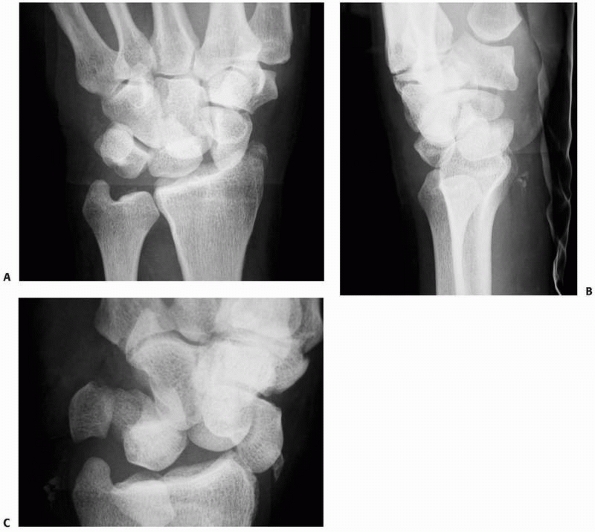

The

four standard views to diagnose an injury are the anteroposterior (AP)

and lateral radiographs, each taken in the exactly neutral position,

and the radial oblique (supinated AP) and ulnar oblique views (Fig. 29-9). These four standard views detect most carpal injuries,67

![]() |

FIGURE 29-9

The four scaphoid views (AP, true lateral, radial oblique, ulnar oblique) detect most of carpal fractures. A fisted AP view can be helpful in detecting scaphoid fractures |